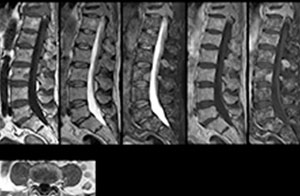

To minimize the time taken to perform scans, rapid MRI examination protocols (ExamCards) were developed, shortening the total scanning time to even less than 10 minutes in some exams. Techniques like mDIXON (modified DIXON) are used for robust capturing of fat-free MRI images in a hectic ED environment.